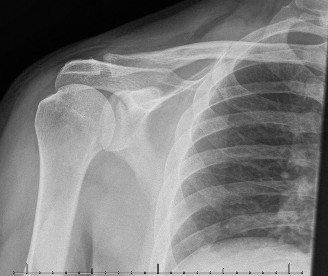

A 21-year-old, right-hand-dominant, male, college swimmer presents to clinic complaining of gradually worsening right shoulder pain for the past 6 months. He notes that his times at swim meets have been slowing with the onset of the pain but that he is still able to swim through the pain. Physical examination reveals: decreased muscle bulk over the infraspinatus fossa of the right shoulder compared with the contralateral side (shown in Fig. 2–64), full active range of motion, strength 4/5 for external rotation but otherwise normal strength, mild pain with cross-body adduction of the right shoulder, and mild tenderness to palpation over the AC joint. Imaging is shown in Figure 2–65.

Figure 2–65